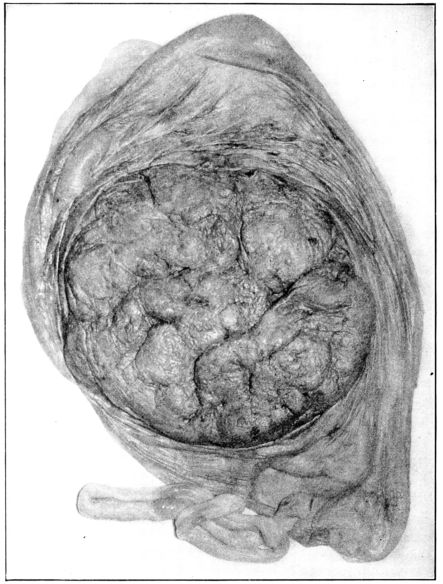

| 22. | Photograph of placental vessels | 72 |

| 23. | Maternal surface of the placenta | 74 |